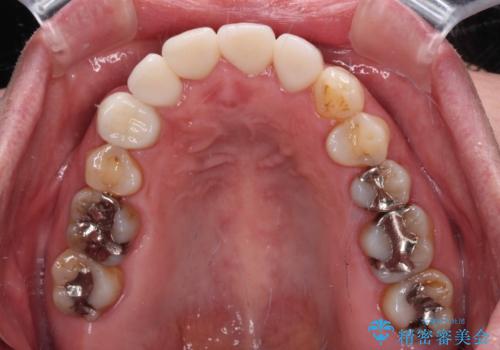

八重歯と形の悪い前歯 矯正治療とセラミック治療

また、当初は予定しておりませんでしたが、歯列が整ったことで前歯の歯の色や形が気になり、矯正治療後にオールセラミッククラウンにて補綴治療することとしました。

あっという間に気になっていた歯列が改善され、自然な口元になり、患者様には大変満足していただきました。